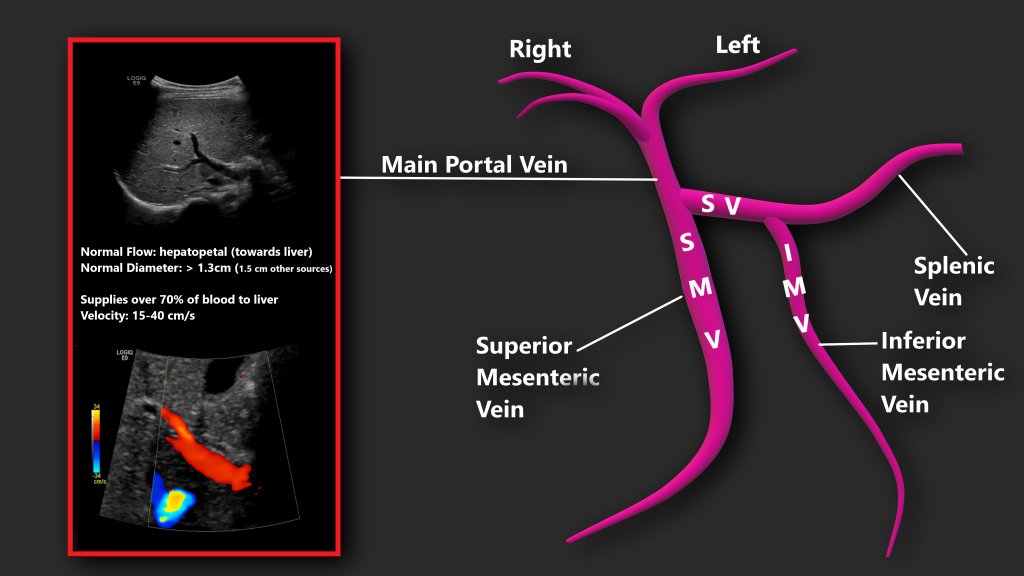

High-resolution digital imaging for detailed cellular analysis.